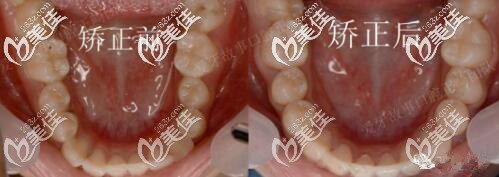

圖四前后牙弓對(duì)比

矯正用了1年半,地包天明顯改善,牙弓也擴(kuò)開(kāi)了。正畸期間口腔護(hù)理很重要,如果出現(xiàn)了口腔有異味或炎癥,就要隔兩到三天使用牙套清潔片把牙套泡一泡,必要時(shí)可用酒精棉片對(duì)牙套進(jìn)行消毒。